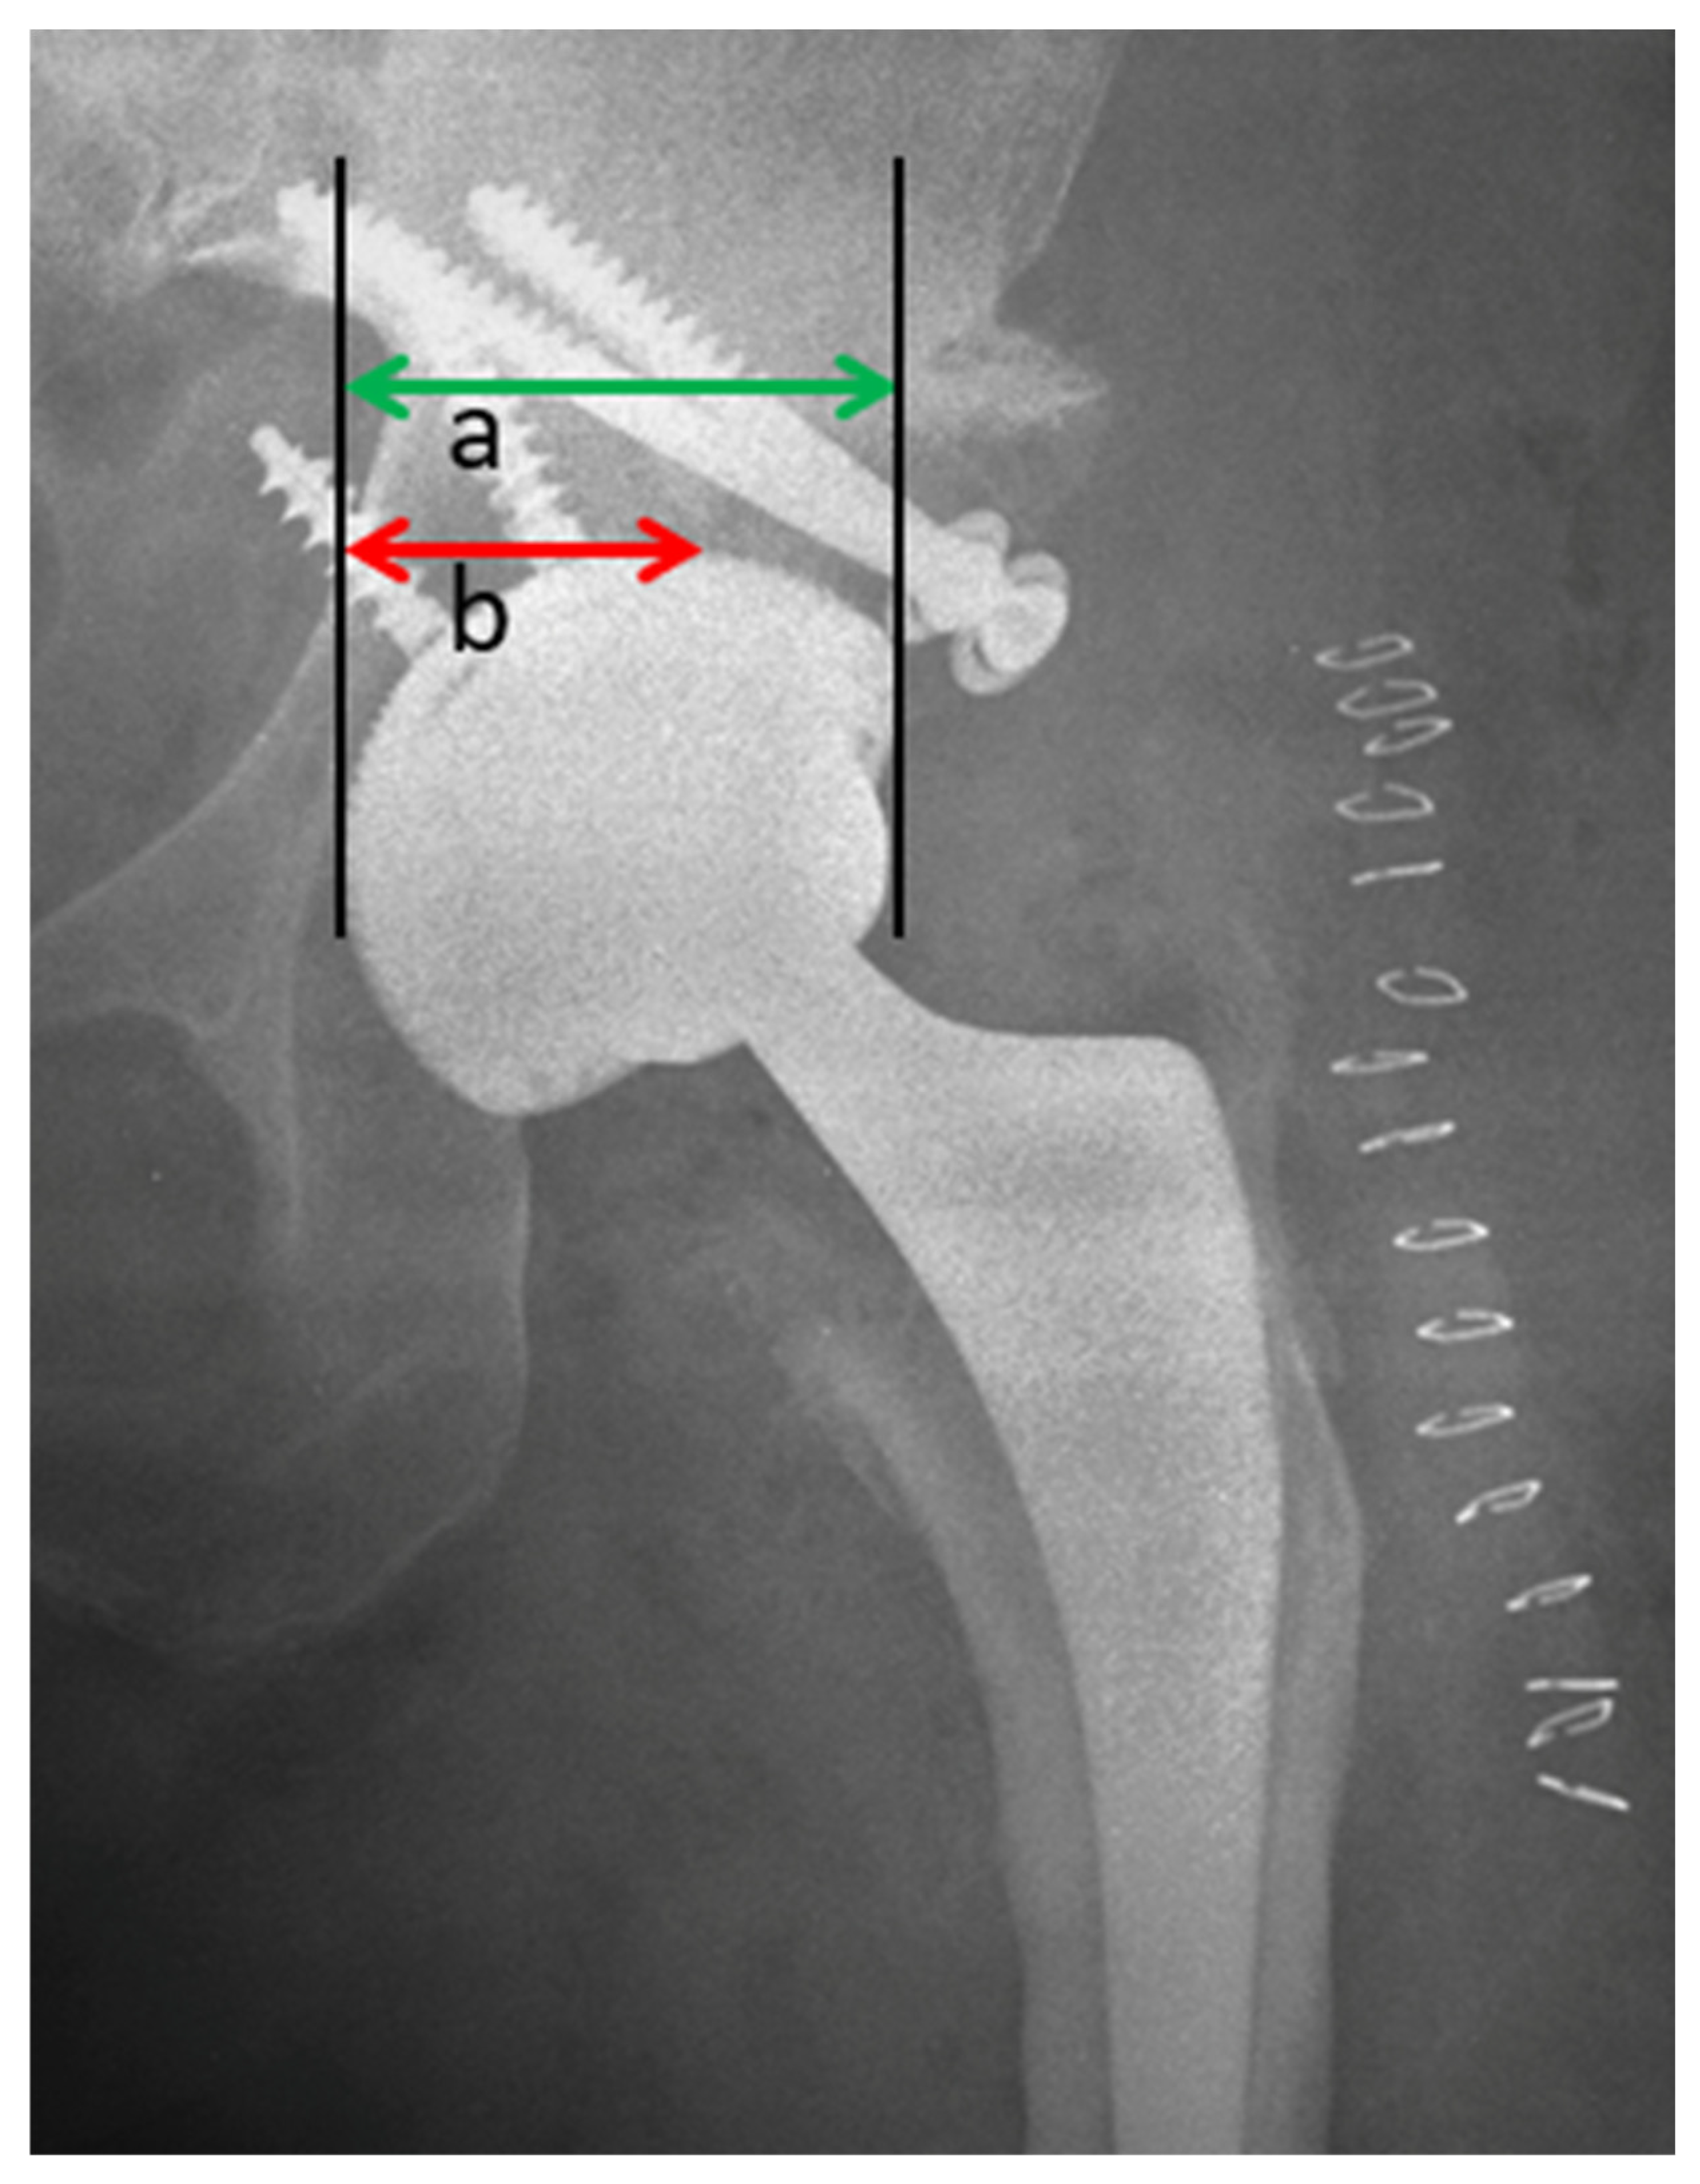

2.2. Radiological Assessment